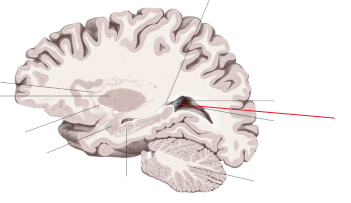

corpus callosum

lobus frontalis

lobus parietalis

lobus occipitalis

lobus temporalis

insula

gyrus cinguli

sulcus centralis

sulcus cinguli

fissura longitudinalis cerebri

tractus olfactorius

fornix